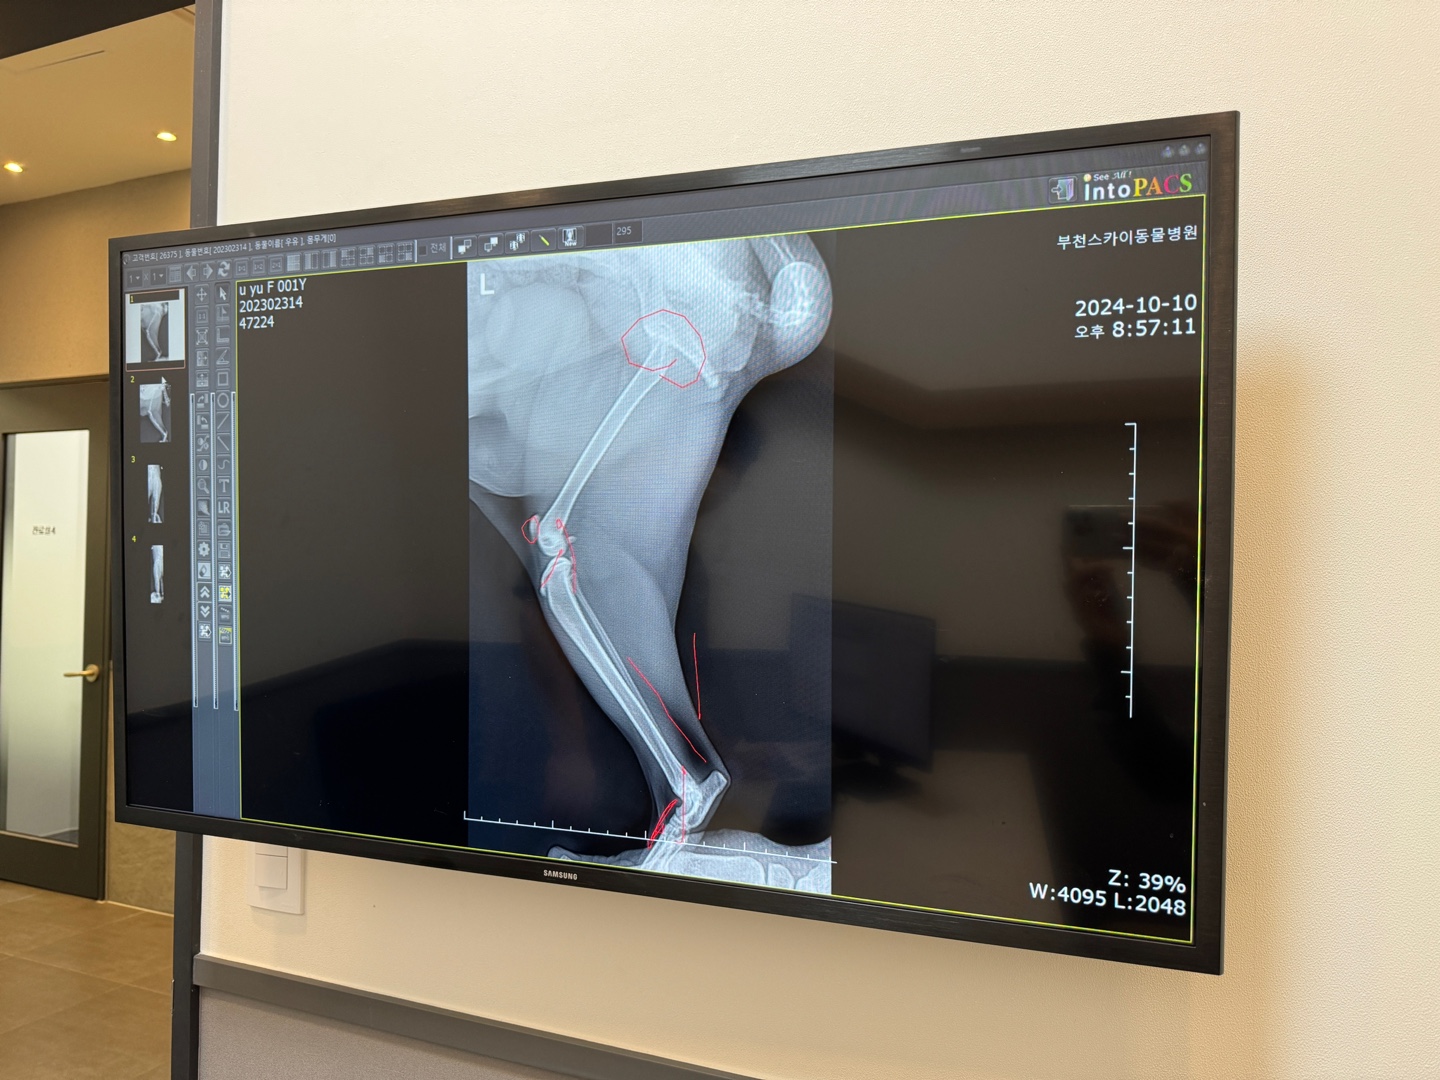

렉돌의 경우 연골에 선천적으로 문제가 있는 종으로 엑스레이상으로는 현재 문제가 되는 점은 나타나지 않는다고 합니다. 엑스레이상 문제없고 떨어지거나 크게 충격받은 일이 없다면 진통제 먹으면서 경과를 지켜보자는 진찰결과였습니다.

엑스레이 찍은 김에 성장판에 대해서도 설명을 해주셨는데 아직 안 닫힌 곳이 있다고....(5KG가 넘는데... 더 클 수 있다는???) 일단, 소염진통제(액상형) 받고 집으로 돌아왔습니다.